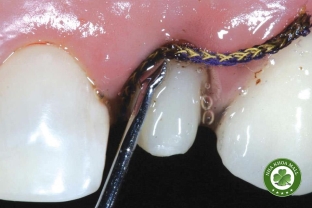

• Nha khoa thẩm mỹ: Tẩy trắng răng, dán sứ veneer, bọc răng sứ.

• Cấy ghép Implant: Công nghệ cấy ghép răng hiện đại, kỹ thuật nâng xoang, ghép xương.